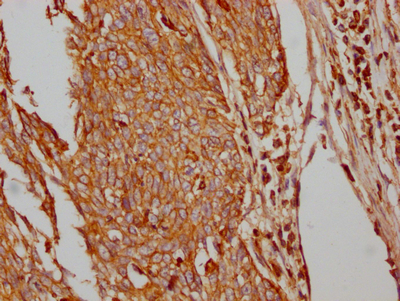

IHC image of CSB-RA297401A0HU diluted at 1:100 and staining in paraffin-embedded human cervical cancer performed on a Leica BondTM system. After dewaxing and hydration, antigen retrieval was mediated by high pressure in a citrate buffer (pH 6.0). Section was blocked with 10% normal goat serum 30min at RT. Then primary antibody (1% BSA) was incubated at 4℃ overnight. The primary is detected by a Goat anti-rabbit IgG polymer labeled by HRP and visualized using 0.05% DAB.

IHC image of CSB-RA297401A0HU diluted at 1:100 and staining in paraffin-embedded human lung cancer performed on a Leica BondTM system. After dewaxing and hydration, antigen retrieval was mediated by high pressure in a citrate buffer (pH 6.0). Section was blocked with 10% normal goat serum 30min at RT. Then primary antibody (1% BSA) was incubated at 4℃ overnight. The primary is detected by a Goat anti-rabbit IgG polymer labeled by HRP and visualized using 0.05% DAB.